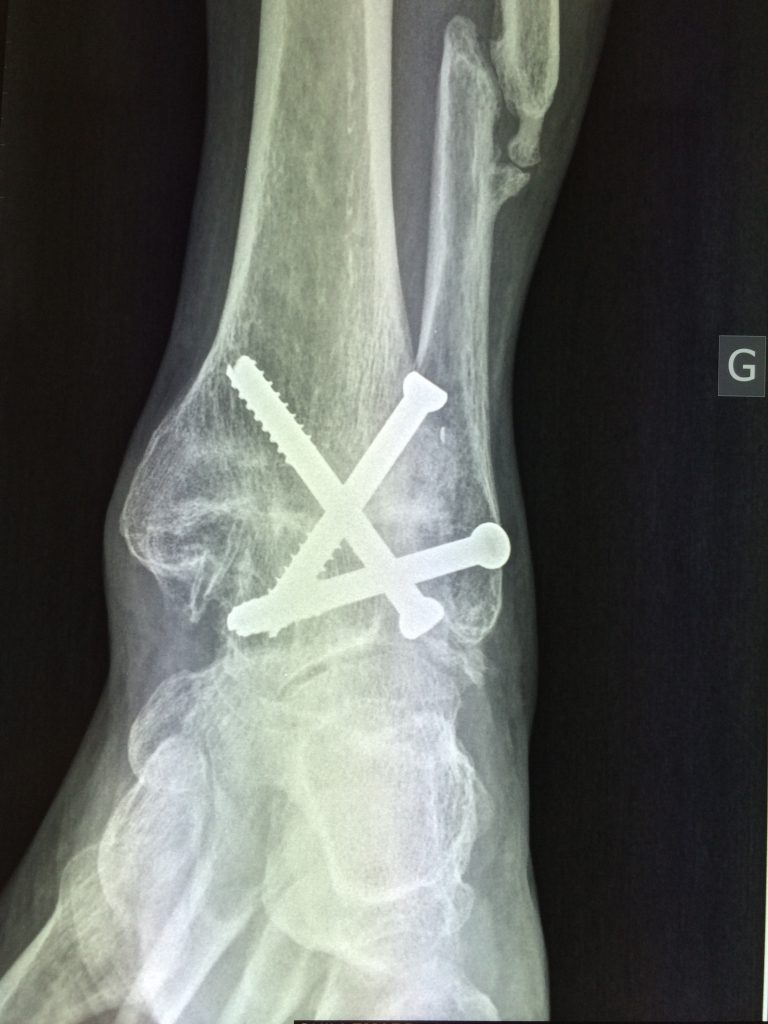

Je nachdem welches Gelenk versteift wurde, resultiert die Versteifung in einem kleineren oder größeren Funktionsdefizit. Hier müssen Versteifungen noch häufiger durchgeführt werden. Lesen Sie alles Wichtige über den Ablauf der Arthrodese, wann sie notwendig ist und welche Risiken sie birgt. Der Eingriff wird bei einer fortgeschrittenen Arthrose durchgeführt, wenn eine Versorgung mit einem künstlichen Gelenk nicht mehr möglich ist.Vorteile einer Arthrodese des Sprunggelenks. Die Arthrodese stellt technisch eine Herausforderung dar und sollte, insbesondere in der Revisionsendoprothetik, aus schließlich von erfahrenen Kniechirurgen durchgeführt werden. Dabei entfernt der Arzt einen der betroffenen Mittelhand-Knochen und ersetzt ihn durch körpereigene Sehnen, etwa die Sehnen des langen Daumenmuskels oder des kurzen Handbeugers. Die beiden Knochenenden werden wie eine Fraktur durch Osteosynthese mit Hilfe von Schrauben, Platten oder Drähten fixiert. 1 Symptome: Gelenkschmerzen und -steifigkeit, Bewegungseinschränkungen, Funktionsstörungen, Schmerzen bei Belastung, Anlaufschmerzen, Verlust der Lebensqualität. Sie umfasst die wichtigsten Anteile des unteren Sprunggelenks: das Gelenk zwischen Sprungbein und Kahnbein (Talonaviculargelenk) und das Gelenk zwischen Sprungbein und . Auch Fehlstellungen der großen Fußzehe, vor allem Hallux valgus und Hallux rigidus, werden in der Regel durch eine Arthrodese in günstiger Gelenkstellung behandelt.

Nutzen sich die . Für die Patienten besteht eine hohe . Schwimmen und . Der Substanzdefekt wird mit einem autologen oder allogenen .Die Arthrodese des Sprunggelenks kann auch mit Hilfe eines Marknagels durchgeführt werden, der Schienbein, Sprungbein und Fersenbein . Vielfach herrscht die Meinung vor, dass man mit steifen Gelenken nicht laufen könne. In unserem Praxisalltag erleben wir seit .